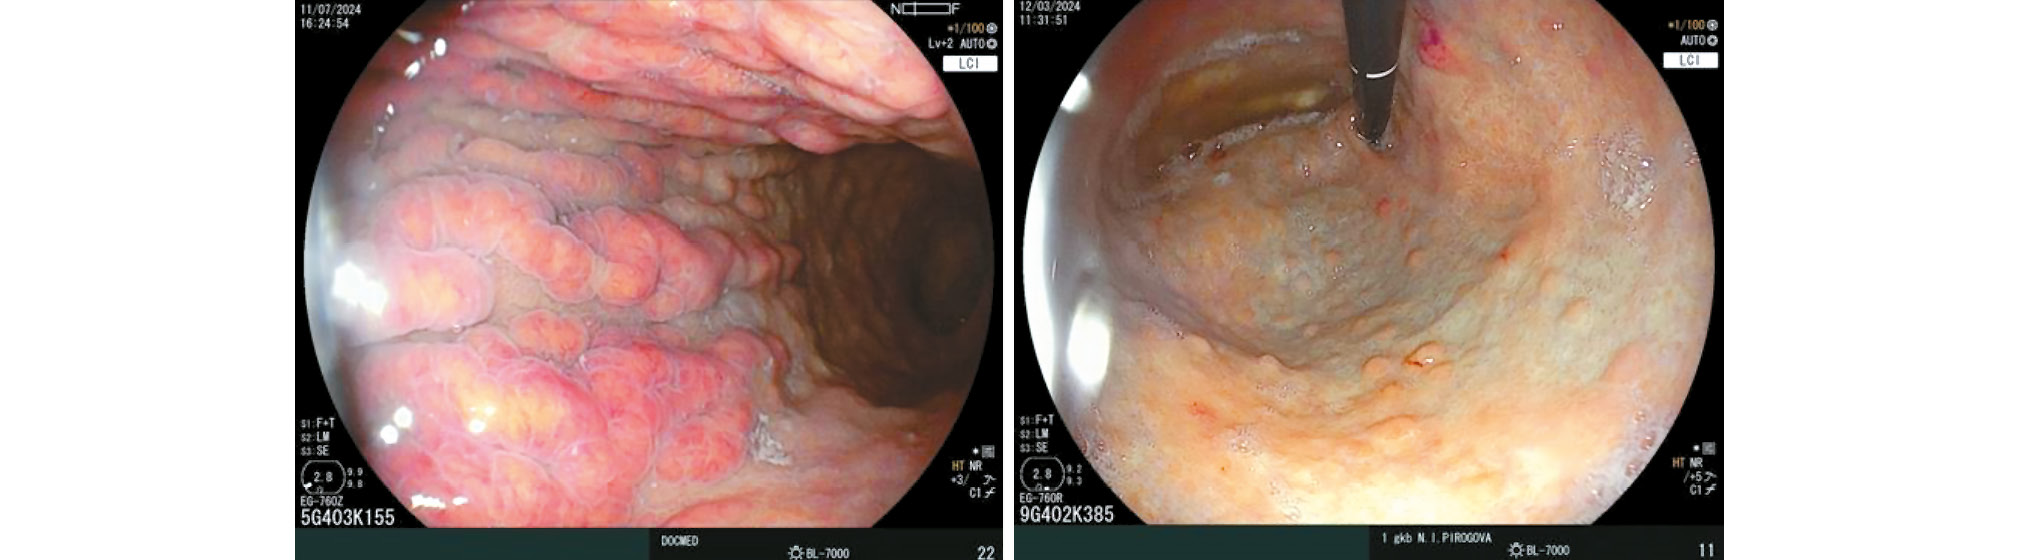

Doyama et al. described the appearance of white spherical structures and glomus-like formations when the gastric body was examined with optical magnification. White spheres, initially identified at the margin of differentiated gastric cancers, represent necrosis and apoptosis of neoplastic cells in dilated fundic glands. In autoimmune gastritis, white spheres were initially described as small whitish protrusions. However, due to the similar endoscopic appearance of these protrusions in cancer and autoimmune gastritis, both findings are now collectively referred to as white spheres (Fig. 5) [43]. The spheres are detected in 32% of cases. Iwamuro et al. examined the morphological substrate of these white spheres and demonstrated that they arise from the blockage of fundic glands by neutrophils, mucus, and necrotic parietal cells [44]. Glomus-like formations in the gastric body result from enterochromaffin-like (ECL) cell hyperplasia. These formations were first described by Drapkina et al. (Fig. 6) [45].

Fig. 5. White globe appearance on the surface of mucosa in white light (a) and in narrow-band mode (b). © Eco-Vector, 2025.

Fig. 6. Glomus-like lesions of the stomach (a), glomus-like lesions with white globe appearance and areas of foveolar hyperplasia (b). © Eco-Vector, 2025.

According to Greenson et al. [46] and Itsuno et al. [47], glomus-like structures larger than 0.5 mm are considered neoplastic changes.